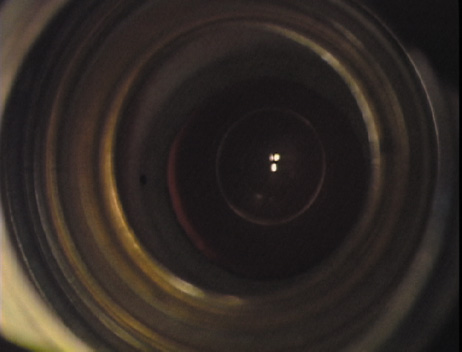

other manufacturers.   Fig. 6. (A)A diamond blade with a preset depth of 600 microns is used

to perform LRIs for routine cataract surgery. (B) An adjustable

depth micrometer blade is used in conjunction with the NAPA nomogram

when treating younger patients. Fig. 6. (A)A diamond blade with a preset depth of 600 microns is used

to perform LRIs for routine cataract surgery. (B) An adjustable

depth micrometer blade is used in conjunction with the NAPA nomogram

when treating younger patients.